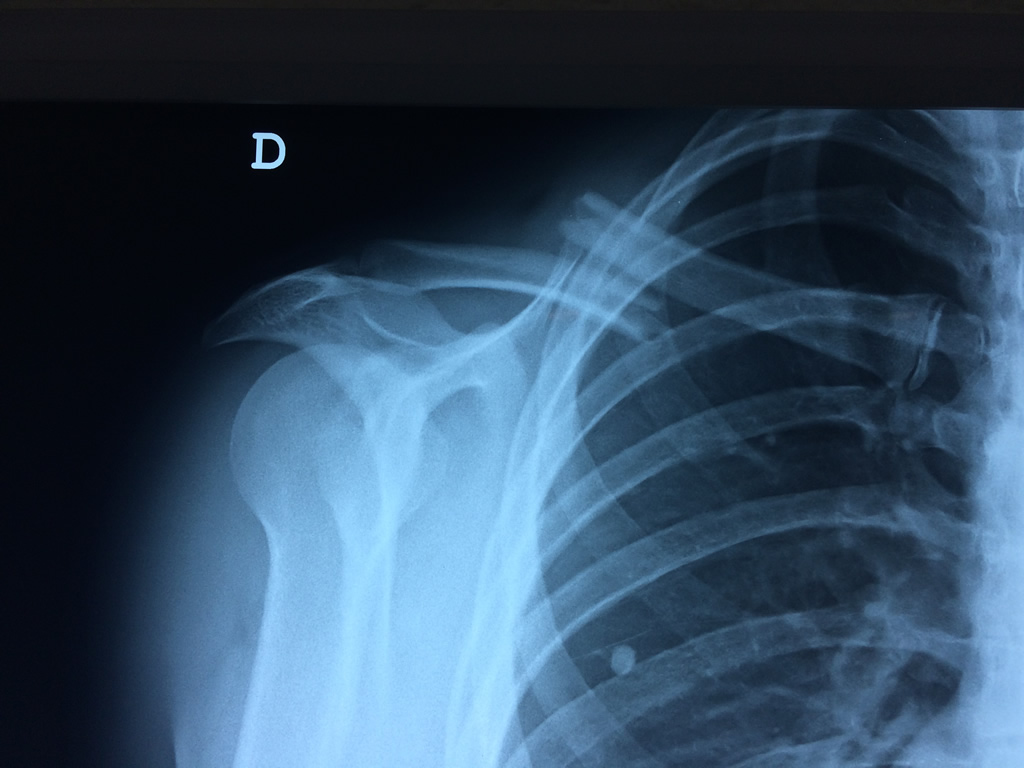

Cirugías de Hombros - Clavícula

La clavícula es un hueso largo, con forma de "S" itálica, situado en la parte anterosuperior del tórax. Junto con la escápula forman la cintura escapular. Se puede palpar por toda su longitud y se extiende del esternón al acromion de la escápula, siguiendo una dirección oblicua lateral y posterior.

Se considera el único medio de unión entre el miembro superior y el tórax. A pesar de su aspecto, similar al de un hueso largo, posee una estructura semejante a la de un hueso plano, ya que carece de epífisis y de diáfisis, lo que la harían entrar dentro de la clasificación de hueso largo. Carece de un canal medular propiamente dicho.